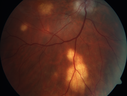

31 year old man with vision loss in the right eye more than the left eye. He has an anaplastic astrocytoma diagnosed 10/2017 the first one was 10/2014. These are different locations. They are treating them with Chemotherapy and Avastin. It might be that one might have spread from the other. He was clean for 3 years. He is on Avastin and Temozolomide but his blood counts have been good. December 2017 he had a herpes superficial infection in the right eye which responded to treatment. The last neurosurgery was October 2017. Going to Duke June 5 and seeing a neuroophthalmologist there. VA OD: Dcc20/40 PH20/25 NccJ5 VA OS: Dcc20/16 PH20/10 NccJ1+ His fundus is presumably nocardia, pneumocystis, aspergillis or cryptococcus. His LP was negative and he was tried on a course of antifungals. He was then lost to followup

Multifocal Choroiditis - Pneumocystis - aspergillis - cryptococcus632 views31 year old male with anaplastic astrocytoma on chemotherapy with mild vision loss in the right eye. LP did not reveal organism. He was placed on a trial of anti-fungal medications and lost to follow-up00000